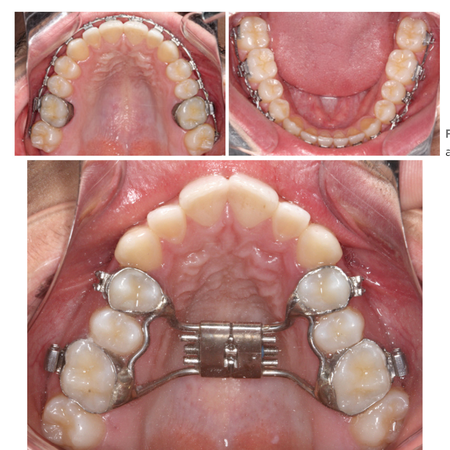

Disjunção palatina anteroposterior e a pré-maxila

OBJETIVO: Fundamentar biologicamente a proposta de disjunção palatina anteroposterior em casos devidamente selecionados. METODOLOGIA: Utilizou-se a amostra de dissertação de mestrado de Trevizan (2018) e suas inferências, para funda...

Disjunção Palatina Disjunção palatina anteroposterior

Anteroposterior palatal disjunction and the premaxilla

OBJECTIVE: To biologically substantiate the proposal of anteroposterior palatal disjunction in properly selected cases. METHODOLOGY: The sample from Trevizan’s (2018) master’s dissertation and its inferences were used to support the...

Palatal disjunction Anteroposterior palatal disjunction

Disyunción palatina anteroposterior y la premaxila

OBJETIVO: Fundamentar biológicamente la disyunción palatina anteroposterior propuesta en casos debidamente seleccionados. METODOLOGÍA: La muestra de la tesis de maestría de Trevizan (2018) y sus inferencias se utilizaron para fundame...

Disyunción palatina Disyunción palatina anteroposterior